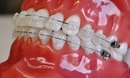

Diş ekimi, kaybedilen dişlerin yerine yapay dişlerin yerleştirilmesi işlemidir. Bu işlem, hem estetik hem de fonksiyonel açıdan birçok avantaj sunmaktadır. Diş ekimi, günümüzde diş hekimliği alanında en yaygın kullanılan yöntemlerden biri haline gelmiştir. Bu makalede, diş ekiminin faydaları detaylı bir şekilde ele alınacaktır. Diş Ekimi Nedir?Diş ekimi, kaybedilen dişlerin yerine cerrahi bir işlemle titanyum veya benzeri malzemelerden yapılan yapay diş köklerinin yerleştirilmesini içeren bir tedavi yöntemidir. Bu işlem, diş kaybının neden olduğu estetik kaygıları gidermenin yanı sıra, çiğneme fonksiyonunu da yeniden kazandırmaktadır. Diş Ekiminin Estetik FaydalarıDiş ekimi, hastaların gülümseme estetiğini önemli ölçüde iyileştirmektedir. Aşağıdaki avantajlar estetik açıdan dikkate değerdir:

Diş Ekimi SüreciDiş ekimi süreci, genellikle birkaç aşamadan oluşur: